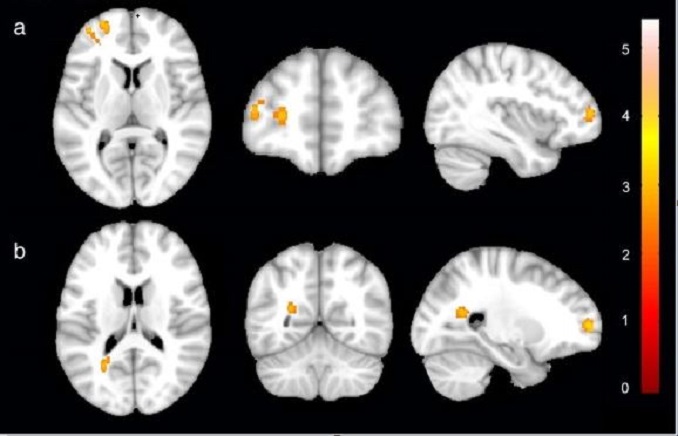

To find out, her team infected mice with various sizes of C. neoformans. They found that in comparison to medium and large cells, the smallest cells preferentially infected the brain. These cells were not only diminutive but differed in other ways. Compared to larger fungal cells, they had unique features on their surface that were similarly important for accessing the brain. They also turned on a different set of genes.

This evidence suggested that the small fungal cells, that Brown dubbed "seed" cells, were not just miniature versions of larger cells. They had undergone a wholesale change.